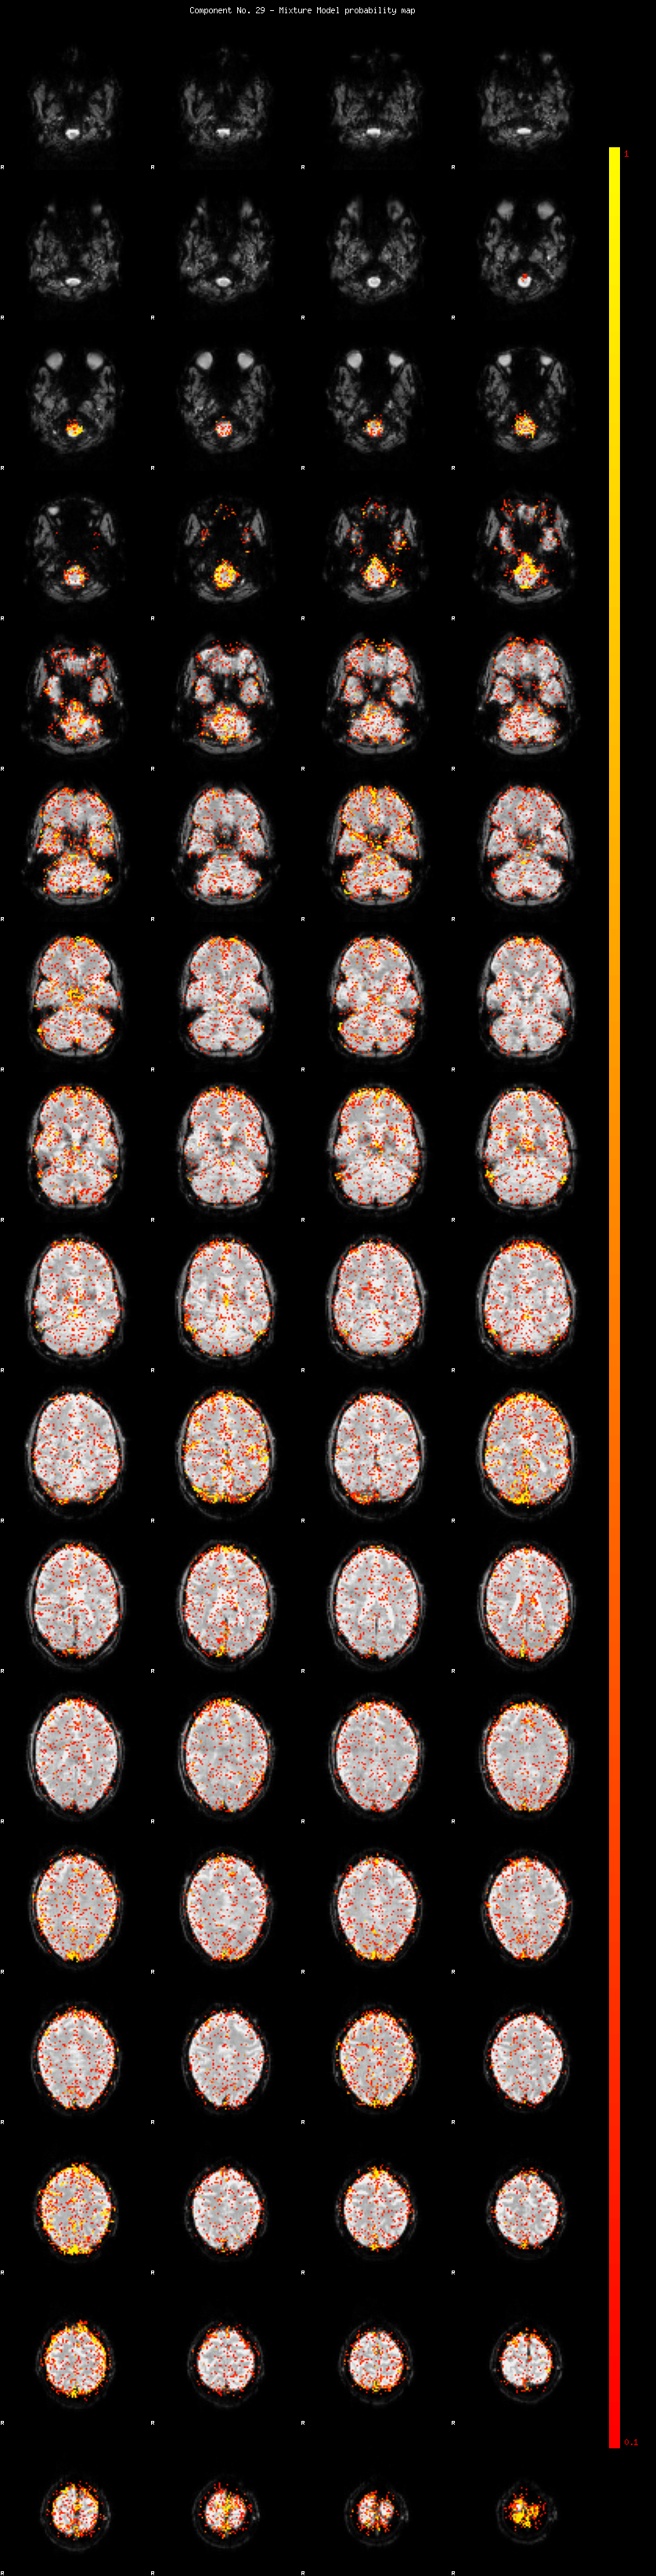

IC_29 Mixture Model fit

Means : -0.000000 2.578522 -2.420810

Vars : 1.000000 2.292167 1.820123

Prop. : 0.921880 0.044007 0.034112